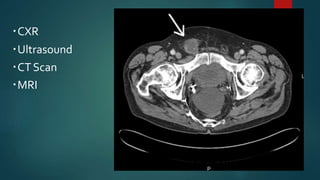

IMAGING

CXR

Ultrasound

CTScan

MRI